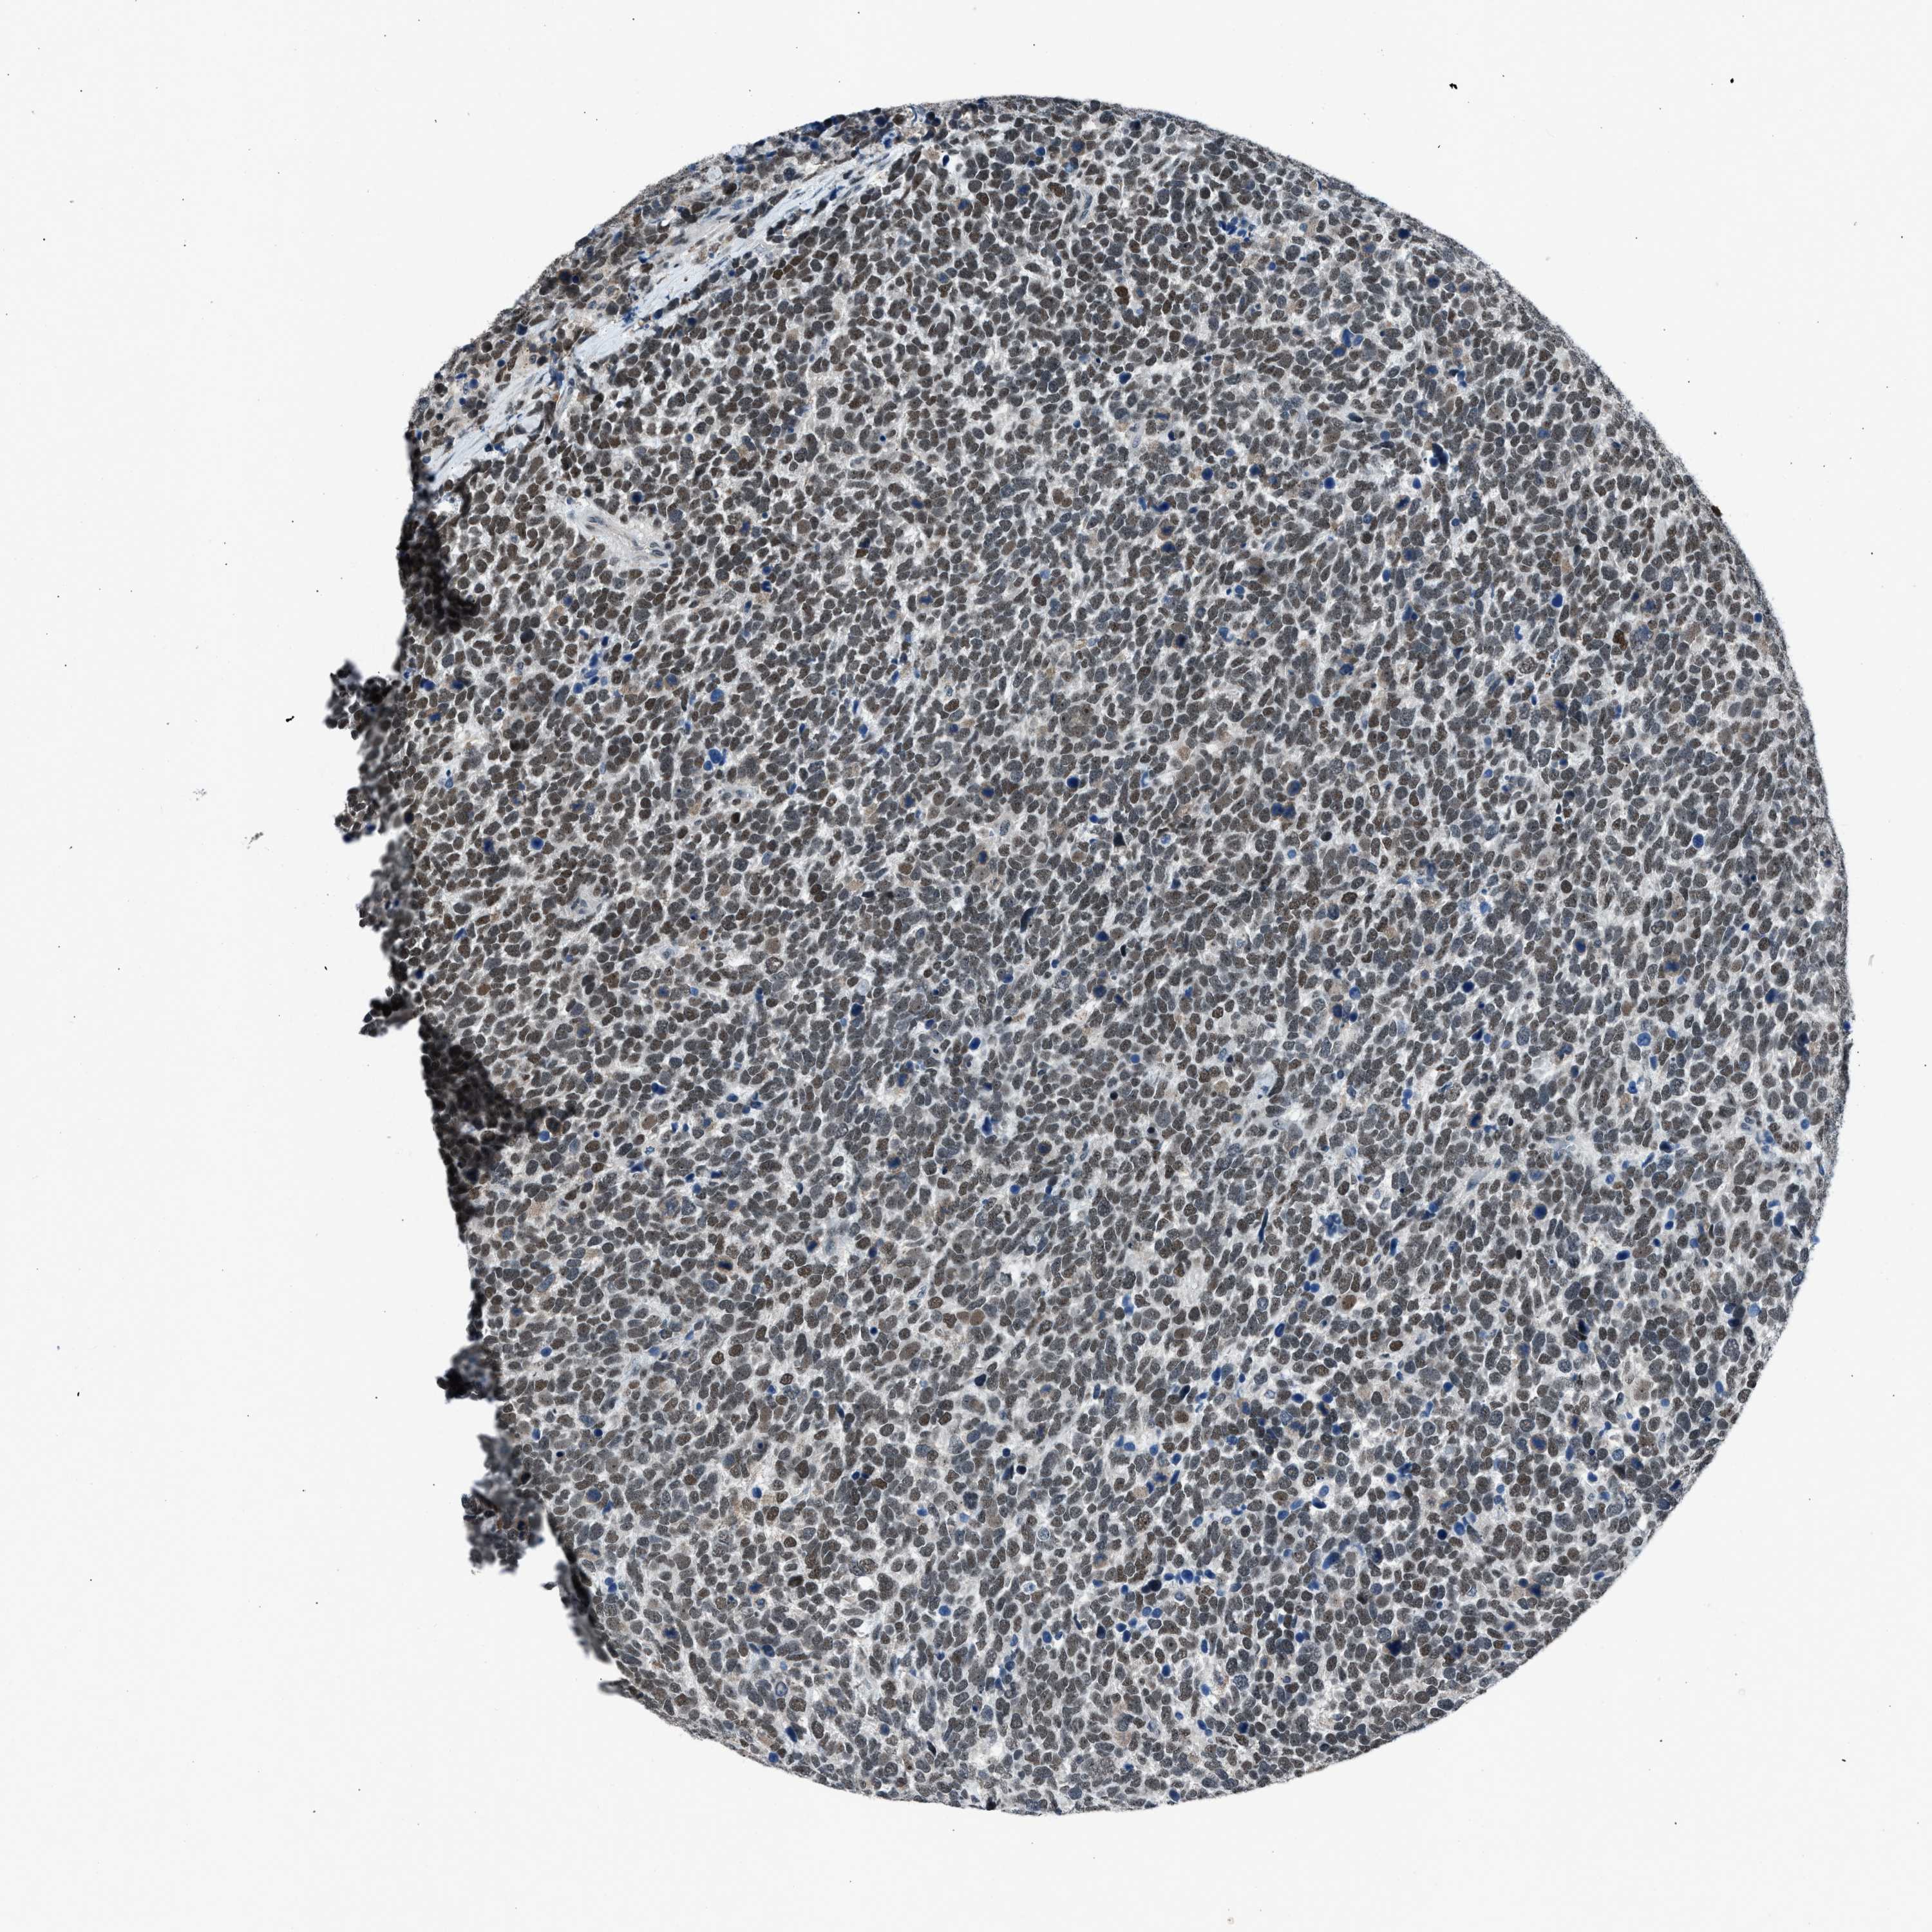

UROTHELIAL CANCER - Protein expressioni

A mouse-over function shows sample information and annotation data. Click on an image to view it in a full screen mode. Samples can be filtered based on level of antibody staining by selecting one or several of the following categories: high, medium, low and not detected. The assay and annotation is described here.

Note that samples used for immunohistochemistry by the Human Protein Atlas do not correspond to samples in the TCGA dataset.

Antibody stainingi

Antibody staining in the annotated cell types in the current human tissue is reported as not detected, low, medium, or high, based on conventional immunohistochemistry profiling in selected tissues. This score is based on the combination of the staining intensity and fraction of stained cells.

Each image is clickable and will lead to virtual microscopy that enables deeper exploration of all samples and also displays staining intensity scores, fraction scores and subcellular localization as well as patient and tissue information for each sample.

Antibody CAB018364

Staining

High

Medium

Low

Not detected

Intensity

Strong

Moderate

Weak

Negative

Quantity

>75%

75%-25%

<25%

None

Location

Nuclear

Cytoplasmic/membranous

Cytoplasmic/membranous,nuclear

Urothelial carcinoma, Low grade

Urothelial carcinoma, High grade